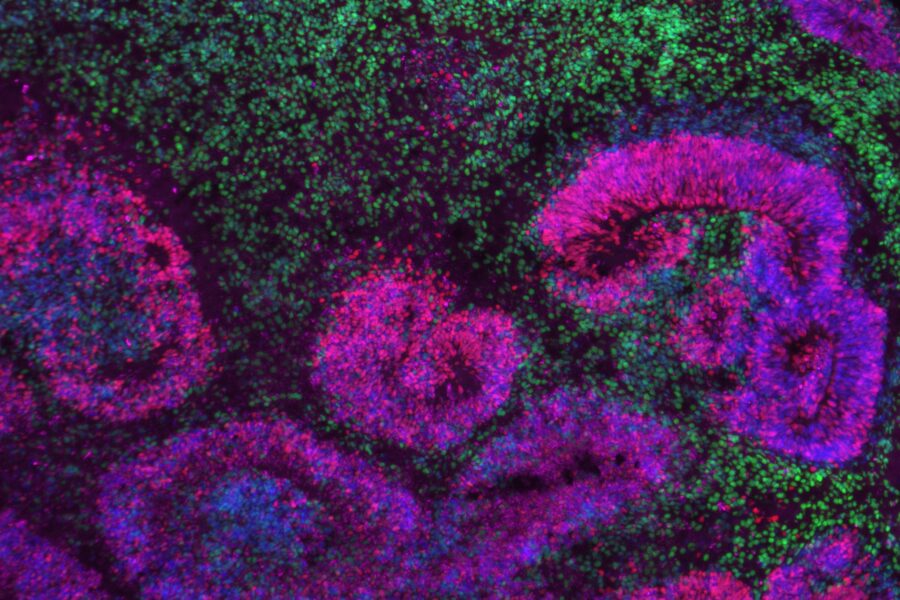

How Studying Cell Fitness in the Early Human Embryo Could Enhance Cancer, Fertility, and Regenerative Medicine Research

UW Institute for Stem Cell & Regenerative Medicine | December 10, 2025

Dr. Min (Mia) Yang is a University of Washington Assistant Professor of Obstetrics & Gynecology…